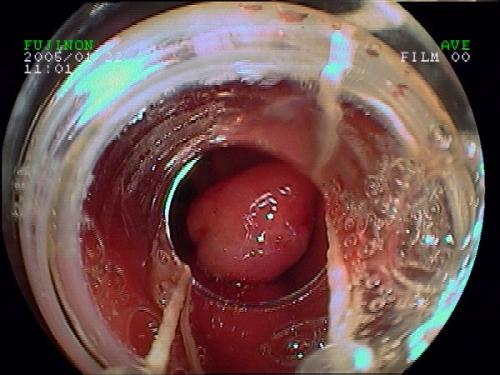

胃大息肉內鏡下套扎術(shù)